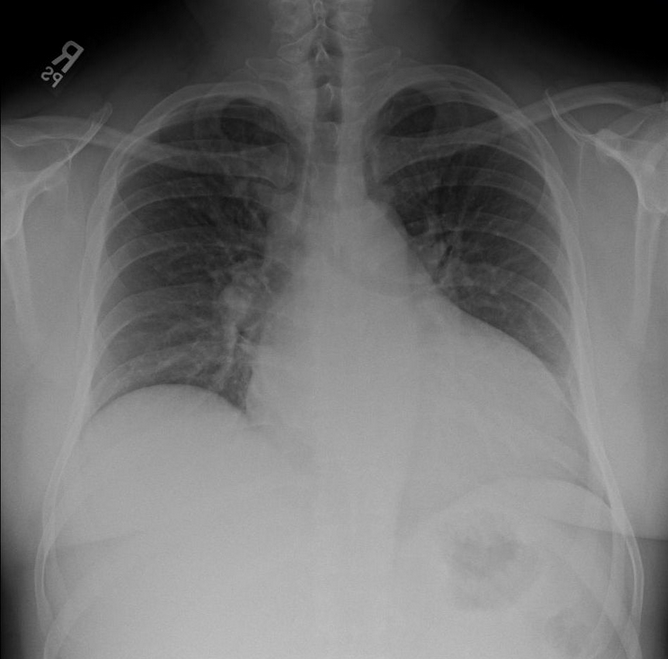

Though it was atypical for the patient to be hypotensive and tachycardic, the presence of a pericardial effusion without tamponade suggested aortic dissection to me.  My attending got on the phone to prepare to transfer the patient while I contacted the radiologist to clear the CT scanner.  Though I attempted to view the descending aorta and aortic outflow tract on a more focused echo in the brief interim through a parasternal approach, I was unable to obtain good windows.  The IVC was plump and the rest of the FAST was negative.  A quick Chest XR was done:

Screen Shot 2013-08-22 at 6.21.01 PM

…..which did not show a wide mediastinum according to radiology.  The patient was whisked away to the CT scanner and within 45 minutes of ED arrival, the diagnosis of a Stanford type A aortic dissection with pericardial effusion (but not tamponade) was confirmed.  This would not have been possible without bedside ultrasound as I think most clinicians would have been falsely reassured by the normal CXR (widened mediastinum only present in 60% of aortic dissections1).